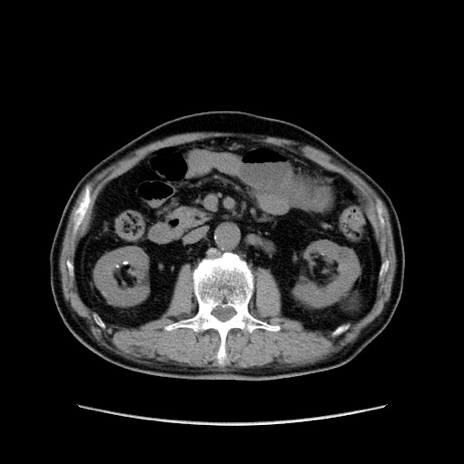

症例24(横断像)

【症例】80歳代男性

【主訴】左側腹部痛、嘔吐

【現病歴】本日早朝より左腹部に痛みあり。昼頃嘔吐認めたため、救急要請。

【既往歴】直腸癌(Mile手術)、胆摘

【身体所見】意識清明、BT 35.9℃、BP 221/93mmHg、SpO2 97%(RA) 、腹部:左ストーマ周囲に限局性の腹部膨隆あり。 膨隆部自発痛・圧痛あり・軟。

【データ】WBC 7700、CRP 0.09